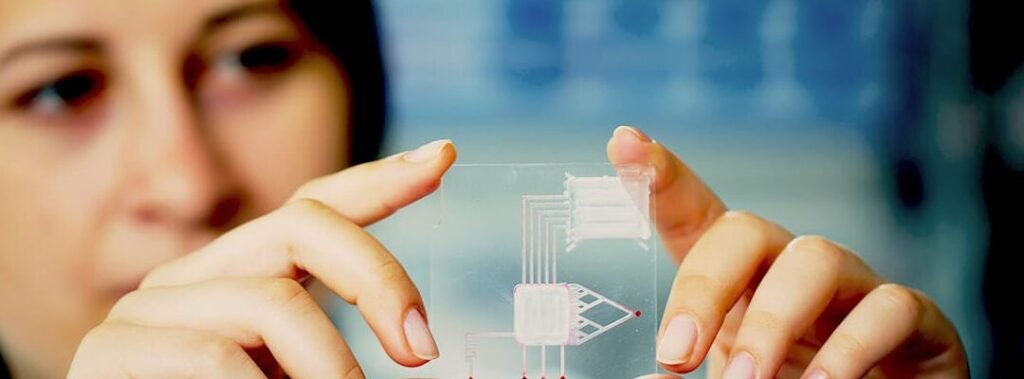

Los avances en nanotecnología han abierto nuevas posibilidades en el campo médico, destacando especialmente los . Estas...

El representa una innovadora frontera en la biotecnología médica, ofreciendo una alternativa accesible y sostenible a los...